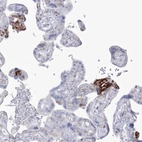

Immunohistochemical staining of human placenta shows moderate to strong positivity in endothelial cells.